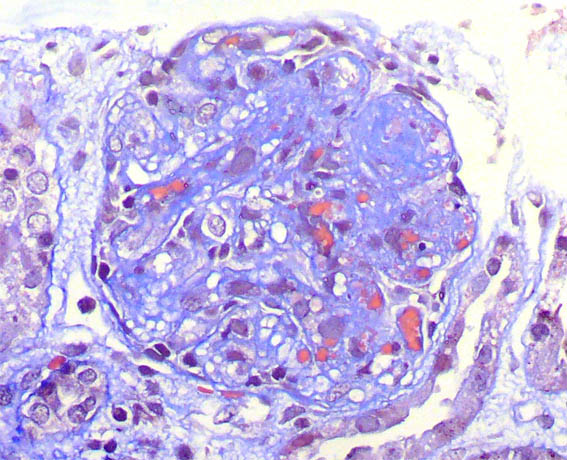

Se hace biopsia renal. Observe las imágenes.

Figura 5.

Tricrómico de Masson, X400.